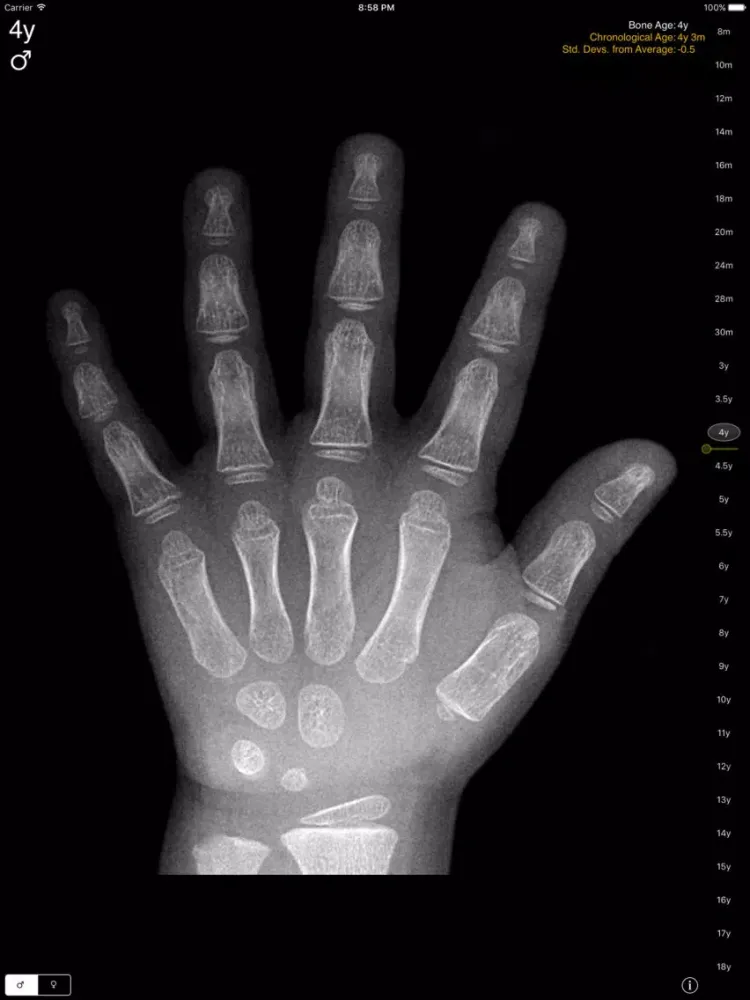

The Gilsanz and Ratib digital Hand Bone Age atlas for iPad, iPhone and iPod Touch brings this essential radiology reference to radiologists, endocrinologists, and pediatricians on the move.

In the past, determination of bone maturity relied on visual evaluation of skeletal development in the hand and wrist, most commonly using the Greulich and Pyle atlas. The Gilsanz and Ratib digital atlas takes advantage of digital imaging and provides a more effective and objective approach to assessment of skeletal maturity.

The atlas integrates the key morphological features of ossification in the bones of the hand and wrist and provides idealized, sex- and age-specific images of skeletal development.

Hand Bone Age: A Digital Atlas of Skeletal Maturity,2e, Vicente Gilsanz, Osman Ratib, ISBN 978-3-642-23761-4